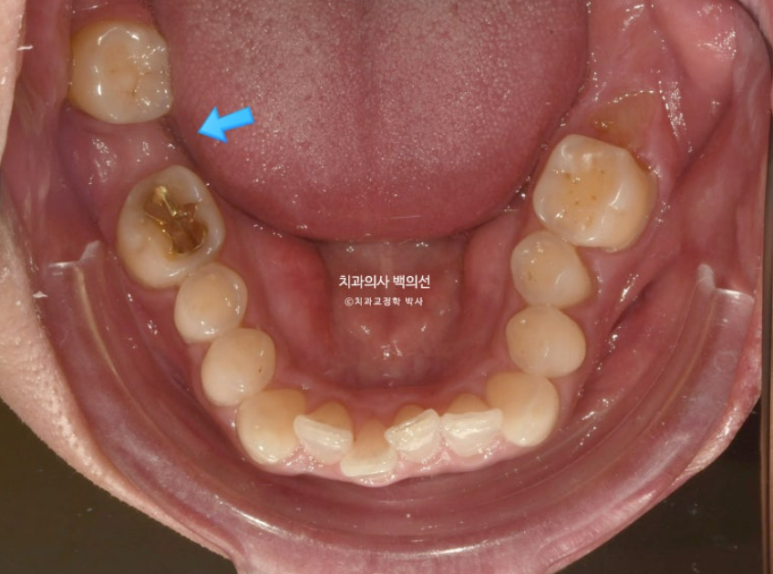

24.05

특히 파란 화살표 공간은 뒤 사랑니가 앞으로 많이 쓰러져서 임플란트가 힘든 상황입니다.

이렇게 좁아져버린 임플란트 공간을 회복하기 위해 쓰러지고 내려온 주변치아들을 정돈하는 교정을 보철교정이라고 합니다.

좁아진 공간과 쓰러진 사랑니는 파노라마 엑스레이에서 확인됩니다.

이런 경우 사랑니를 빼버리면 간단하게 해결이 되지만, 이미 상해서 빠진 이가 많은 상태인데다가 사랑니가 잘 나와 대합치과 교합까지 잘 되는 상태라, 사랑니를 최대한 보존해서 쓰기로 합니다.